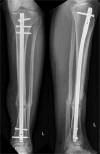

Critical size segmental bone defects represent a challenging problem. Recently, personalized, structured three-dimensional graft cages have been developed to improve ingrowth of autologous bone material and reduce resorption. A 44-year-old patient presented with an open tibial shaft fracture after a motorcycle incident with minor bone loss. Following intramedullary nailing, an acute infection developed that required removal of ~4 cm bone in a circular mode. After multiple interventions, a personalized 3D-printed graft cage was implanted and filled with autologous bone material, harvested by intramedullary reaming from the ipsilateral femur. Ten months postoperatively, the patient is completely pain free and shows good clinical and radiological status. In conclusion, use of a 3D-printed graft cage in combination with Reamer Irrigator Aspirator (RIA) might represent a new additional feature for larger bone defects to avoid gravity or perfusion related resorption of large area defects.